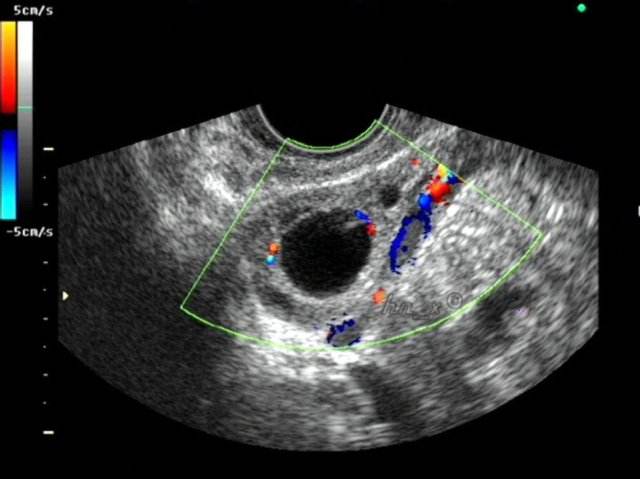

在月经周期的前半期——卵泡期,在雌激素作用下。通常有几个卵泡相继发育,逐渐长大,我们通过B超监测,会发现在近排卵期,这些卵泡中总有一个个头最大,并且在它破裂排卵后其它卵泡相继被吸收消失,我们把这个头较大、发育较成熟的卵泡叫作优势卵泡。

如果月经正常为30天,在月经第十天起卵泡长到1.0以上可算为优势卵泡。随后的几天里,优势卵泡会增大至18mm左右,成为成熟卵泡。到月经后的14天左右,卵泡内的卵细胞和卵泡液会被挤压排出,也就是备孕女性最期待的时刻--排卵!

成熟的卵子一般是20mm以上,最小的在18mm以上才正常。从16mm开始,再经过2-3天,就会发育成20mm的卵泡,卵子排出。卵泡呈圆形或者椭圆形,直径达到18-25mm,低于或者大于这个卵泡大小正常值,都会影响正常排卵。 外形饱满,呈圆形或椭圆形,内壁薄而清晰,这样的“好卵泡”排卵后更容易受孕。

卵泡就像种子,饱满、圆润才好,如果卵泡的两个径限差距≥3mm就叫扁卵泡,如果B超显示15mm× 20mm,则说明卵泡质量不佳。另外,如果一侧的卵巢同时有多个卵泡发育,但没有明显的优势卵泡,可能是内分泌紊乱引起的,如多囊卵巢综合征等。这种情况最终只会导致哪个卵泡都长不大、长不好,很难正常排卵与受孕。